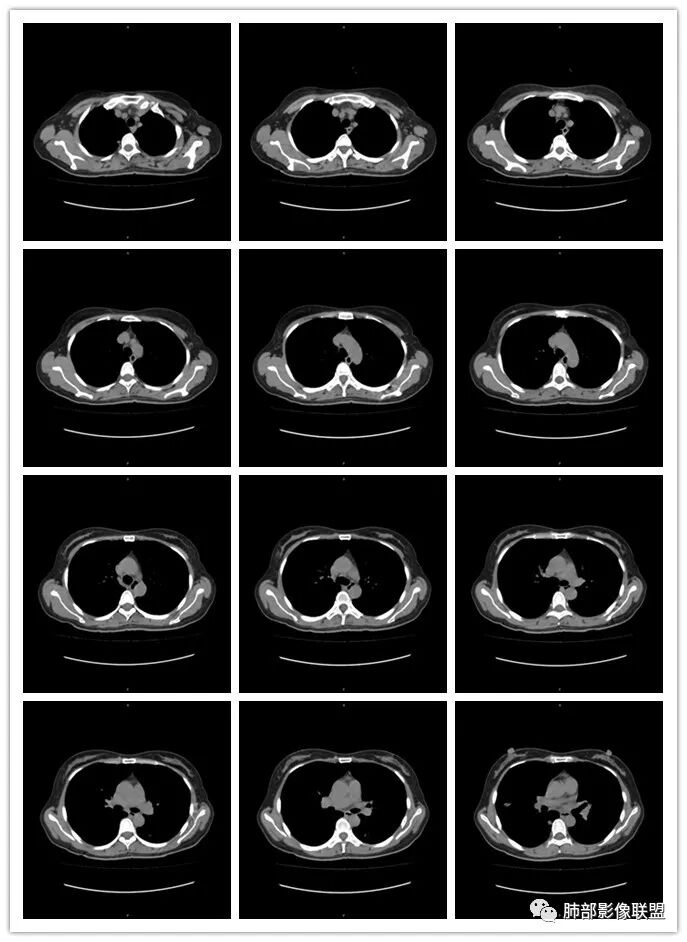

1、临床特点:46岁女性,体检发现双肺结节。白细胞数、中性粒细胞数及CRP升高。

2、影像特点:两肺可见多发结节影、斑片影及条索影,密度均匀柔和,未见明确空洞,边界不清。病灶有沿着支气管血管束分布或随机趋势,部分病灶周围可见晕征,并可见典型的“雪糕征”,支气管血管束增粗。

3、病例小结:中年女性,实验室检查炎性指标升高,两肺多发病灶沿着支气管血管束分布+支气管血管束的间质增厚,容易先考虑感染性病变。临床表现逍遥,双肺多发,不符合常见的社区肺炎,隐球菌胸膜下常见,磨玻璃晕,晕内细长软毛刺,多发病灶常形态密度相仿(蘑菇兄弟)。

病史有重要参考意义,鼻窦炎临床常见,但手术病理肉芽肿炎则意义非同寻常。本例缺乏肾功能检查结果。